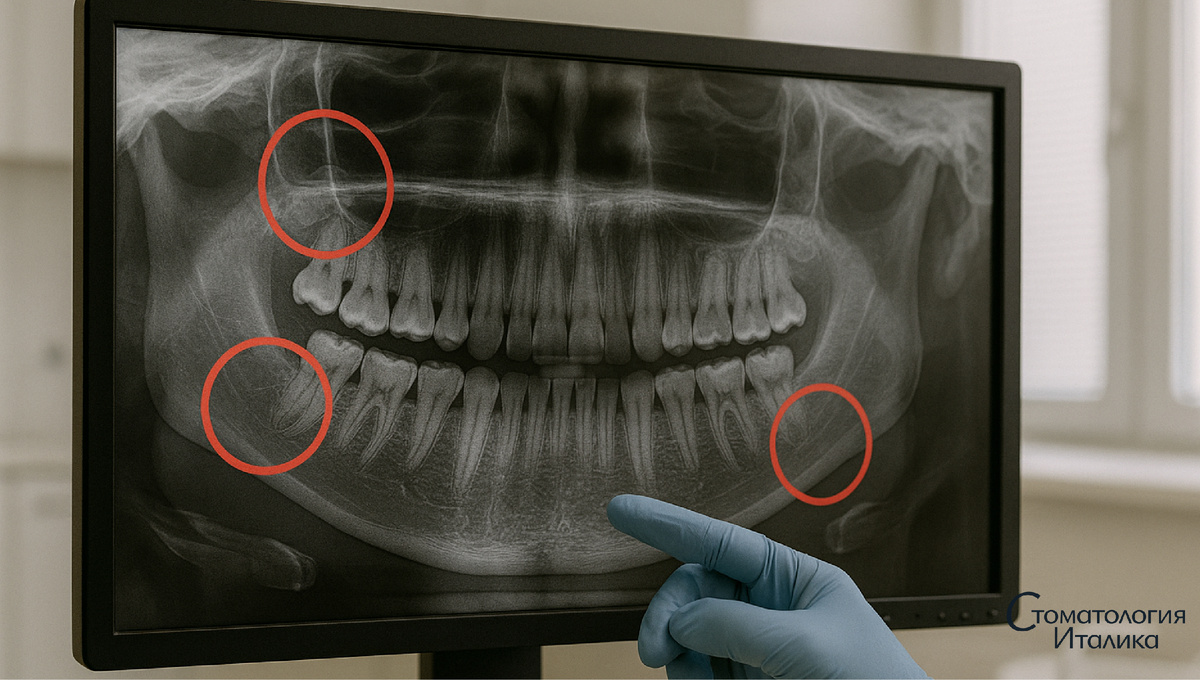

В Telegram-канале мы говорим честно - где имплант действительно нужен, а где можно спасти свой зуб.

Показываем реальные кейсы, снимки, работу под микроскопом и объясняем без маркетинговых лозунгов.